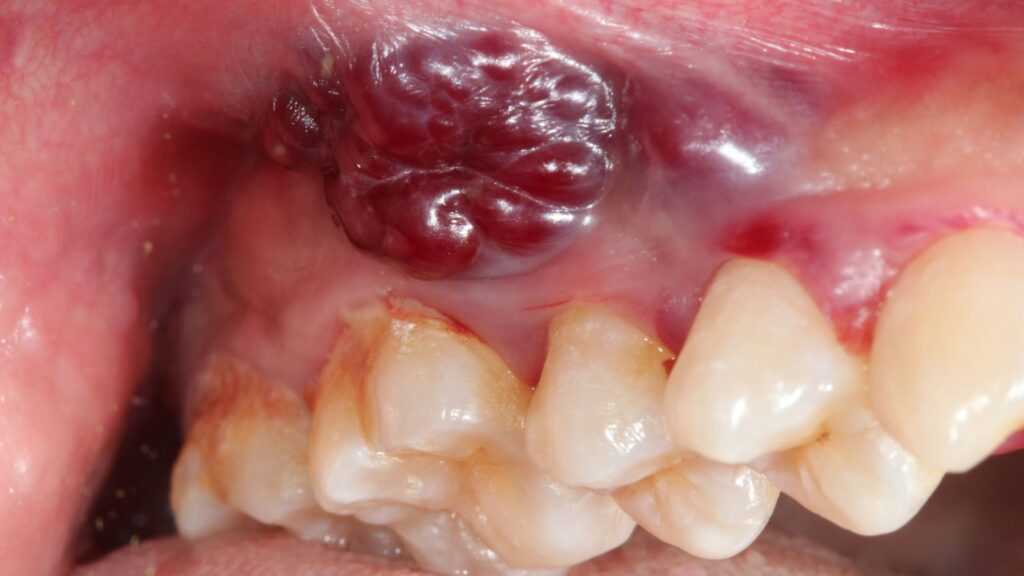

Oral cancer can start as a small patch or an ulcer and may resemble a common problem. The only difference between a common problem and cancer is that oral cancer lesions do not resolve independently and do not respond to standard antibiotic therapy or topical ointments. These lesions may spread rapidly and can occupy the mouth if left untreated.